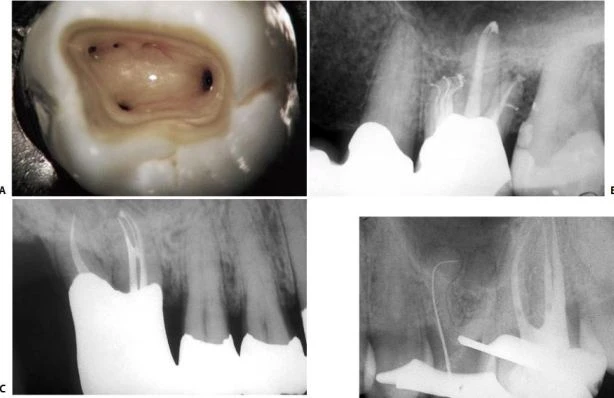

Răng cối nhỏ thứ nhất hàm trên

Buồng tủy của răng cối nhỏ thứ nhất hàm trên được định hướng theo chiều ngoài trong. Trong đa số các trường hợp chúng có hai sừng tủy -tương ứng cũng có hai ống tủy – bên dưới các múi răng (hình 11.43). Hướng của xoang tủy vì vậy cũng theo chiều ngoài trong, không phải là gần xa như trong tạo xoang trám.

Hai sừng tủy nằm trong đỉnh của múi tương ứng. Miệng của hai ống tủy cũng gần như nằm tương ứng với sừng tủy. Vì vậy, nhìn chung ta có thể sửa soạn một xoang tủy tốt mà không phạm đến múi răng. Điểm đi vào của mũi khoan là phần giữa rãnh trung tâm (hình 11.44 A), và khoan theo hướng song song với trục của răng (hình 10.44 B, C).

Hình 11.43. Răng cối nhỏ thứ nhất hàm trên cắt theo chiều dọc, thấy hình ảnh sừng tủy và miệng ống tủy.

Hình 11.44. A. Mặt nhai của răng cối nhỏ thứ nhất trên. B. Mũi khoan kim cương tròn xuyên qua phần giữa rãnh trung tâm, phá vỡ trần buồng tủy. C. Hình ảnh X-quang. D. Đưa mũi khoan đã dùng trước đó vào lỗ đã được mở ở giai đoạn xuyên qua, trên đường đi ra, chạy mũi khoan để lấy đi những phầncòn lại của trần buồng tủy. E. Hình ảnh X-quang (còn tiếp).

Khi xuyên qua với một mũi khoan kim cương tròn và tay khoan siêu tốc, cần kết hợp chuyển động mũi khoan theo chiều ngoài trong để phát họa đường viền mặt nhai của xoang tủy. Cần ghi nhớ rằng: trong giai đoạn xuyên qua, mũi khoan không nên tạo một xoang tủy dạng ống với các thành song song, mà nên kết hợp với chuyển động xoắn ốc để tạo hình dạng phễu khi khoan xuống lớp ngà. Khi đã xuyên vào đến buồng tủy, sử dụng tay khoan chậm để lấy phần ngà còn lại sau giai đoạn xuyên qua (hình 11.44 D, E).

Dùng mũi khoan đầu trơn với tay khoan siêu tốc tạo hình dáng của xoang mở tủy ở giai đoạn hoàn thành và làm loe (hình 11.44 F,G). Hình dạng của xoang mở tủy khi hoàn thành có hình trứng với đường kính lớn hơn theo chiều ngoài trong và nó thường không liên quan đến đỉnh múi (hình 11.44 H, I). Việc nó có liên quan đến đỉnh múi hay không tùy thuộc vào góc phân kỳ giữa hai chân răng và của hai ống tủy: nếu càng phân kỳ thì xoang tủy càng nhỏ, nếu càng song song thì xoang tủy càng có khả năng phạm đến múi răng. Hai ống tủy thường giao nhau tại một rãnh cạn, ta có thể xác định được rãnh này nếu kiểm tra kỹ sàn buồng tủy (hình 11.45).

. Hình 11.44. (tiếp theo) F. Dùng mũi khoan kim cương ở giai đoạn hoàn thành và làm loe. G. Hình ảnh X-quang của giai đoạn hoàn thành và làm loe. H. Xoang tủy đã hoàn thành. I. Hình ảnh X-quang: múi vẫn còn nguyên.

Hình 11.45. Miệng của hai ống tủy của răng cối nhỏ thứ nhất trên thường giao nhau bởi một rãnh trên sàn tủy.